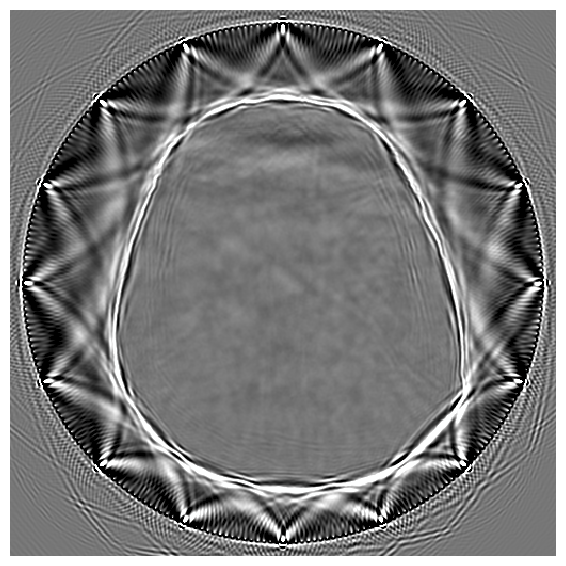

To overcome the end-to-end inference problem, we apply one iteration of ASPIRE by training a CNF on pairs, , where the ’s represent the score-based summary statistics at the fiducial points, , taken to be the uniform water velocity for all samples. An example of this initial summary statistic is shown in Figure 8. While the outer edge of the skull is reasonably well delineated, the inner edge of the skull is still poorly resolved and details inside the skull are mostly absent. However, the inference based on these initial summary statistics, shown in Figure 9, present a significant improvement over the baseline (cf. Figure 7), despite the presence of strong imaging artifacts in the summary statistics. The improvements concern the skull’s structure in particular, although details within the skull remain elusive due to the summary statistic’s limited information. To enhance fidelity further, ASPIRE 2 (shorthand for ASPIRE at iteration ) is applied by recalculating the score at the new posterior mean estimate for each training sample. Given these new training pairs, the next CNF is trained. While posterior sampling is efficient with CNFs (using Equation 4), recalculation of the score for each sample is computationally intensive, a topic we address in Section 6.6.